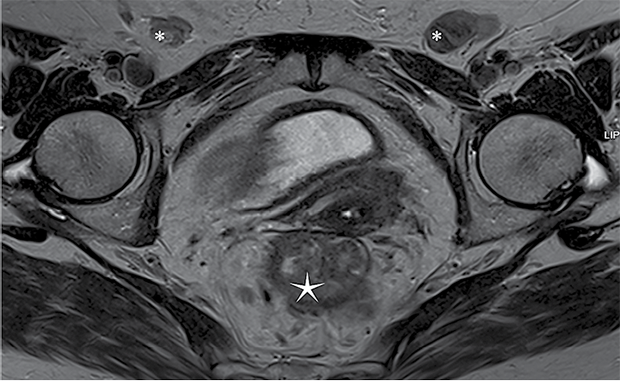

A 76-year-old woman with type II diabetes mellitus and arterial hypertension presented with complaints of rectal bleeding during defecation. Earlier, she had reported itching and lesions in the vulvar region, leading to outpatient evaluation for vulvar carcinoma. A biopsy confirmed keratinizing squamous cell carcinoma G1, unrelated to HPV. Cancer marker tests were performed: CA19-9 level was 38.6 U/mL, and CEA level was 46.6 ng/mL. Contrast-enhanced computed tomography (CT) of the chest, abdomen, and pelvis revealed tumor-like masses involving the labia minora and vagina, as well as suspicious changes in the rectum. Pathological lymph nodes were identified in the inguinal region, measuring up to 3.4x1.7 cm, and pararectally, up to 1 cm in size. Fibrocolonoscopy revealed a circumferential, ulcerated, lumen-narrowing tumor extending from 5 cm to 15 cm above the anal verge. Biopsy from the rectal tumor confirmed adenocarcinoma in situ, unclassified. For further assessment, magnetic resonance imaging (MRI) with intravenous contrast was performed (Figure 1). A tumor measuring approximately 7.9 cm in length was detected in the middle third of the rectum, growing into the intestinal lumen and invading all layers of the rectal wall in certain areas. The tumor exhibited DWI restriction features. Several lymph nodes in the mesorectum appeared pathological. According to MRI imaging findings, the rectal cancer is classified as cT3N1, MRF (‒).

Figure 1. MRI

* ‒ clusters of enlarged lymph nodes, ‒ cancerous mass in rectal region.